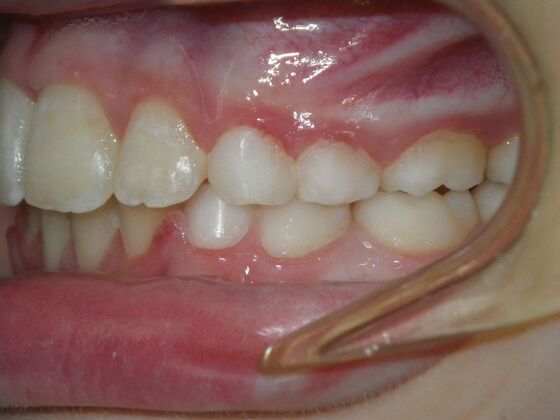

This sweet patient presented with constricted upper and lower arches and blocked out, rotated upper and lower anterior teeth. The upper centrals were leaning backward and had the lower arch captured preventing anterior advancement. Treatment was begun on the upper arch first, followed with placement of lower lip bumper to allow for lateral and anterior development of lower arch. Eventually placed lower brackets with strategic slenderizing of primary teeth to allow permanent incisor to assume their proper placement. All accomplished within 12 months and straight-wire appliances.